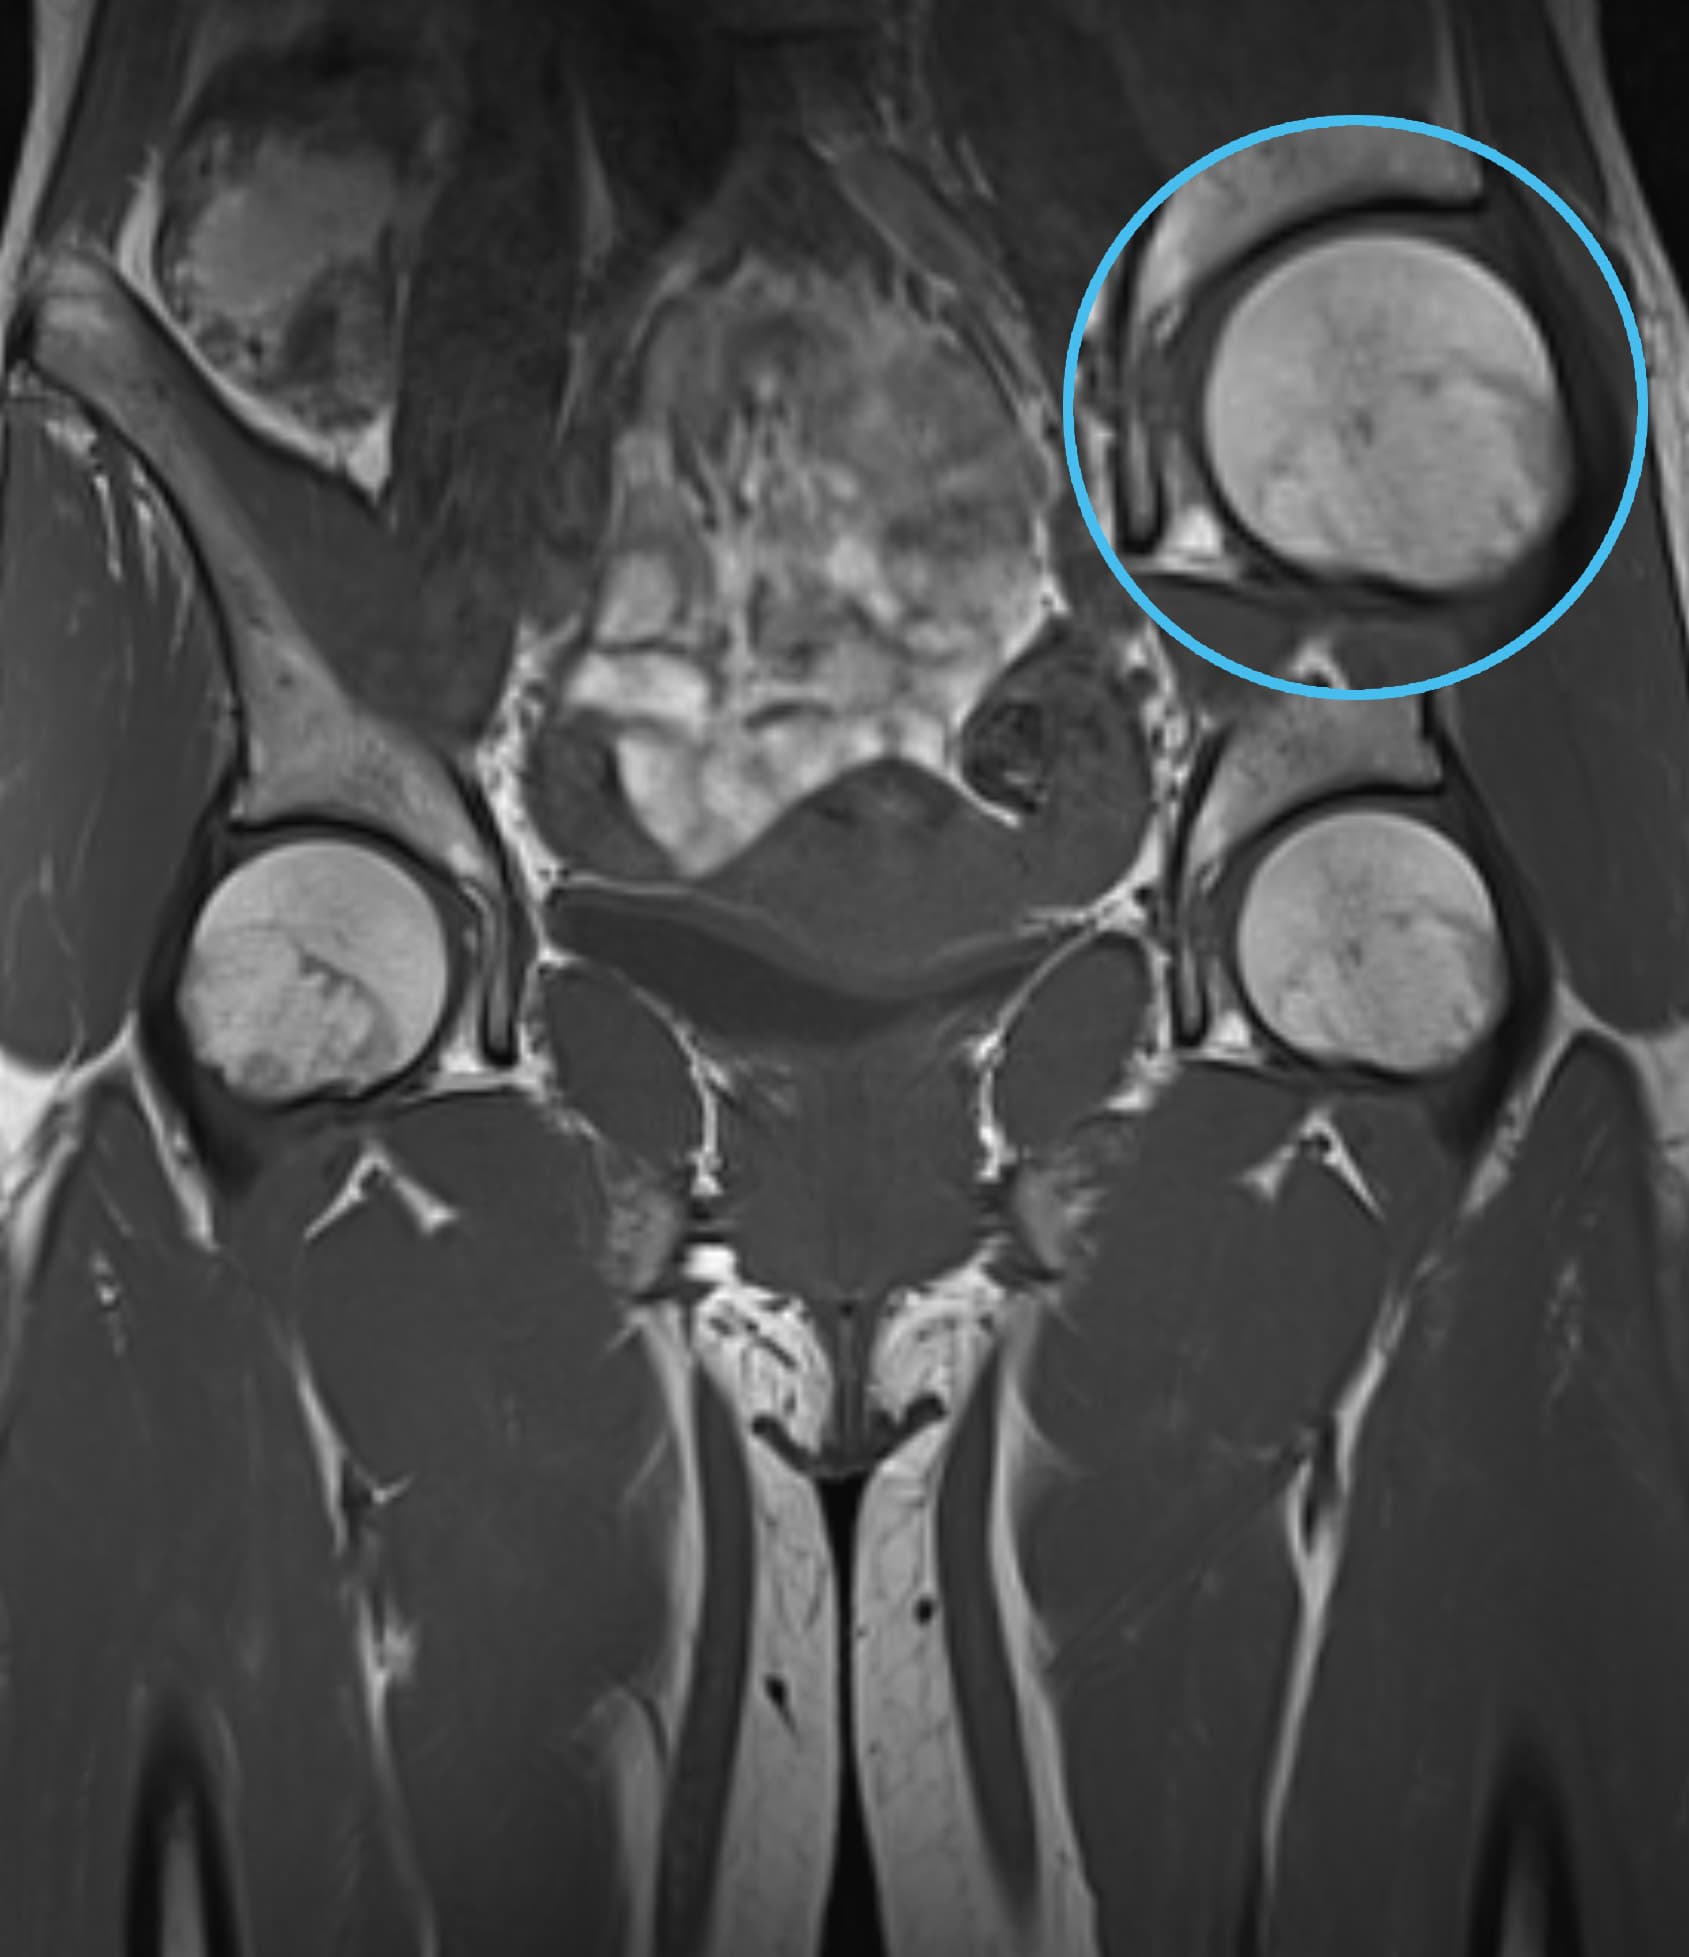

Δείτε πραγματικά παραδείγματα του SwiftMR™ σε διάφορα συστήματα MRI και ανατομικές περιοχές

Scan time 03:14

Scan time 02:07